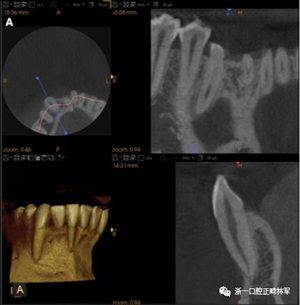

臨床檢查顯示固定保持器完好,弓絲沒有斷裂(圖13)。在下頜右側中切牙唇側和鄰近側切牙的舌側注意到有牙齦退縮。這些牙齒在退縮方向上存在顯著的扭矩差異。下頜的左側尖牙頰側錯位,而右側尖牙舌側傾斜。三維射線照片證實了下頜右側尖牙面?zhèn)妊啦酃菃适?,右側中切牙的喪失程度較輕。右側側切牙根也從舌側骨面上扭轉出來(圖14)。

圖14.三維立體圖像:A,面部和B,切牙根部的舌側,剛取出固定舌側保持器后。